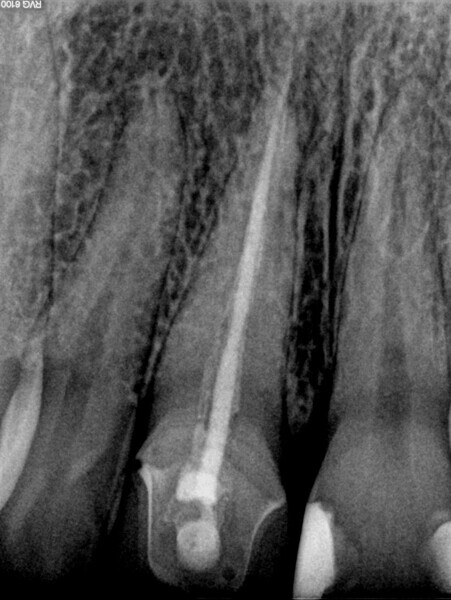

Fig. 3: Pre-op radiograph of tooth #46 showed a large area affected by periapical periodontitis going up into the furcation.